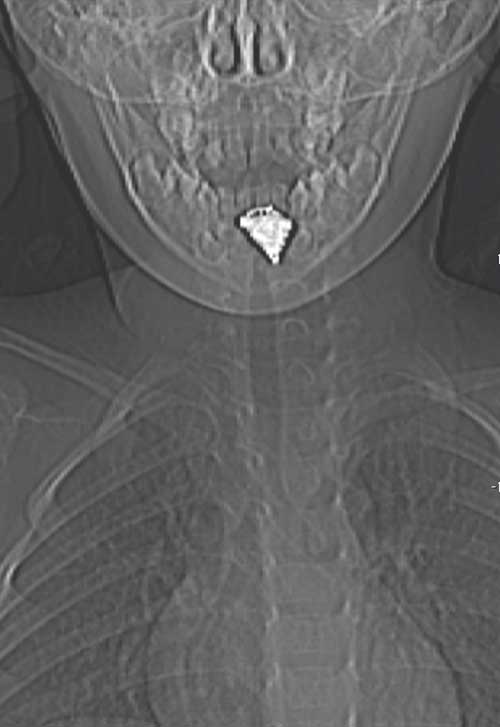

C. � un bambino di 2 anni, giunge in Pronto Soccorso con una storia, incominciata 7 giorni prima, di faringodinia insorta improvvisamente, associata a febbre (38,5 �C) difficilmente controllabile con l�antipiretico, disfagia, scialorrea e dolore al collo. Conside rata tale clinica, si era deciso di ricoverare il bambino presso la divisione pediatrica di riferimento. L�esame obiettivo aveva mostrato la presenza di torcicollo con flessione del capo verso destra, in posizione antalgica. Gli esami di laboratorio avevano evidenziato una leucocitosi neutrofila (GB 22440 di cui 19300 neutrofili) e una Proteina C-Reattiva elevata (13 mg/dl). C. era stato sottoposto a una visita ORL che non aveva mostrato elementi significativi. Nel frattempo era stata avviata empiricamente la terapia antibiotica con ceftriaxone endoven a (1,3 g) che aveva portato a un netto miglioramento della sintomatologia gi� dopo 24 ore: il bambino si era sfebbrato, non aveva lamentato pi� dolore al collo n� disfagia e gli indici di flogosi si erano negativizzati. Tuttavia, al quinto giorno dall�inizio della terapia antibiotica, il piccolo presenta nuovamente dolore al collo, disfagia e scialorrea, sebbene persista apiressia e non ci sia un rialzo degli indici di flogosi. Con questa storia si decide il trasferimento presso il nostro Istituto. Al suo arrivo si presenta in buone condizioni generali ma molto sofferente. L�esame obiettivo e l�endoscopia non evidenziano alcun elemento di rilievo. Nel sospetto di un ascesso retrofaringeo, viene eseguita la TC (Figure 1 e 2).

Figura 1. TC in sezione coronale. | Figura 2. TC in sezione sagittale.

La TC rimane dunque il Gold Standard per la diagnosi che �

stata fondamentale anche per evidenziare la presenza del corpo

estraneo.